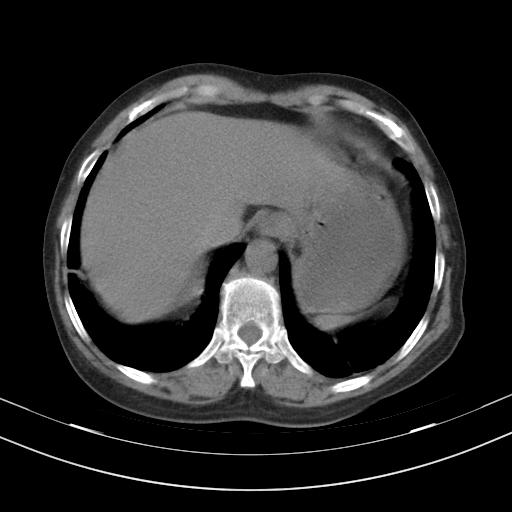

老年女性,嗜睡3天,意识模糊。轻咳,无发热。

1)两肺感染性病变;建议抗炎治疗后复查。2)纵隔淋巴结肿大。3)左侧胸腔积液。

1)先考虑两肺感染性病变;建议抗炎治疗后复查。

2)纵隔淋巴结肿大。

3)左侧胸腔积液。